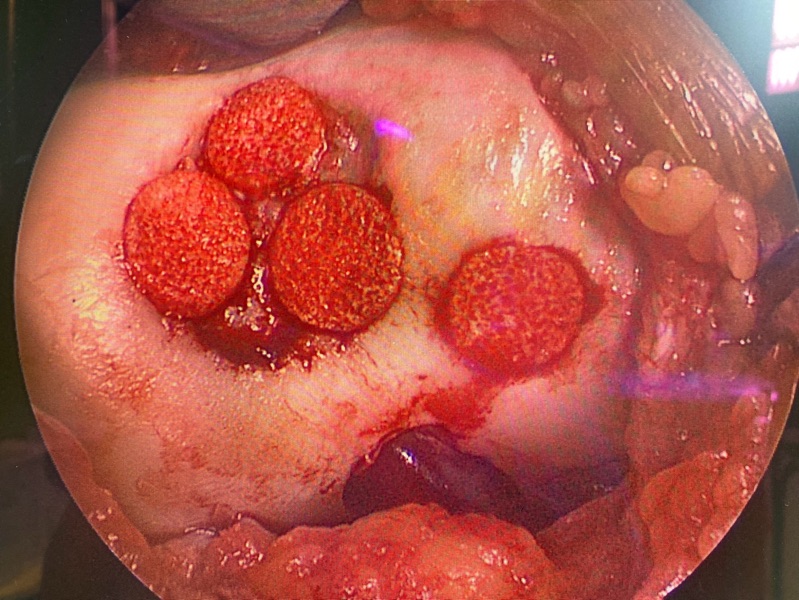

一位二十多歲年輕女性,因籃球運動膝蓋撞擊,導致滑車軟骨局部剝離。經MRI檢查確認為 ICRS Grade III 軟骨缺損。考量患者不願意接受多次手術,我選擇使用一次性自體軟骨修復技術。術後半年,疼痛大幅改善,膝蓋屈伸順暢,MRI 追蹤亦顯示缺損區域已填補良好。

上圖:清創並準備好接下來要植入軟骨載體的區域